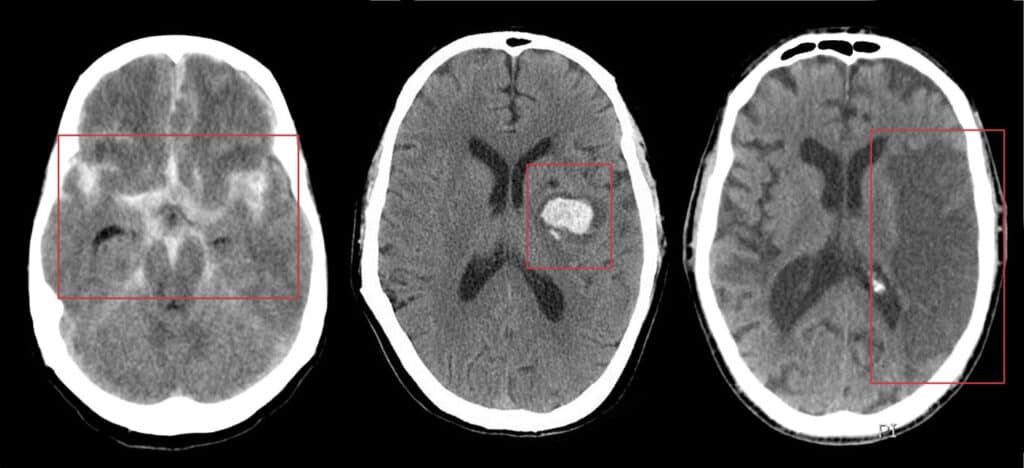

O diagnóstico do AVC hemorrágico é baseado na história clínica, nos sintomas, no exame neurológico e em exames de imagem, como tomografia computadorizada ou ressonância magnética do crânio.

Como os sintomas do AVC isquêmico e do AVC hemorrágico são muitos parecidos, só o exame de imagem permite diferenciar os dois, além de permitir ver o local e a extensão do sangramento.

É também umas das informações que o neurologista especialista em AVC usa para identificar a provável causa.

Depois de confirmado o diagnóstico de AVCH, é importante definir a causa do sangramento, pois o tratamento pode mudar. Para isso, outros exames podem ser indicados, como: